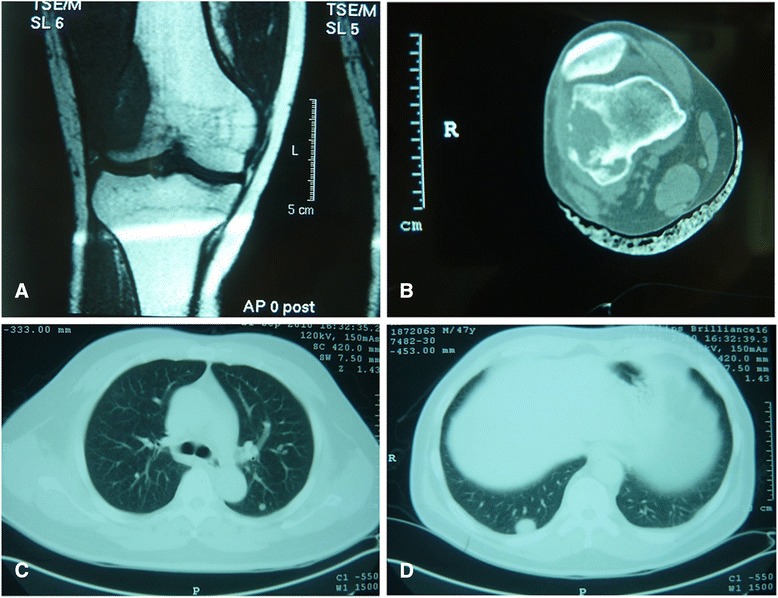

A 47-year-old male presented with a 2-year history of pain and progressive swelling of his left thigh. Computed tomography (CT) scan and magnetic resonance imaging (MRI) of the left lower limb revealed an osteolytic lesion in the distal femur (Figs. 1a and b), measuring 5.2 × 3.2 × 2.6 cm in size. The lesion showed destruction of the cortex with extension into the surrounding skeletal muscle. Curettage of the lesion was performed which was initially reported as a clear cell tumor with recommendation for the exclusion of a metastatic clear cell carcinoma. No evidence of a primary tumor in any site elsewhere was identified by subsequent systematic examinations. However, CT scan of the chest revealed multiple nodules in bilateral lungs which were confirmed as metastatic by CT-guided core needle biopsy (Figs. 1c and d). The patient was treated with conservative palliative radiotherapy and systemic chemotherapy. He was alive with the disease at 3.5 year follow up.

Fig. 1.

Radiology. Magnetic resonance imaging scan shows an osteolytic lesion in the distal femur (a). CT scan demonstrates cortical destruction and extension into adjacent soft tissue (b). Chest CT shows metastatic disease in bilateral lungs (c,d)